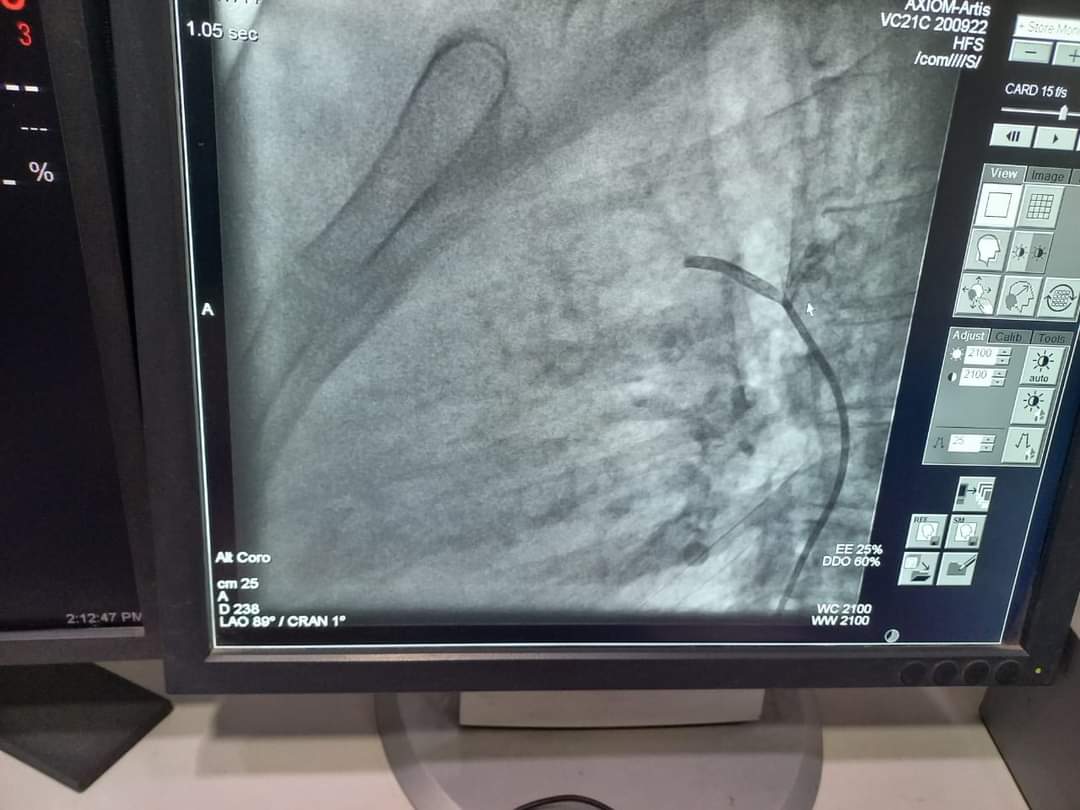

أعلنت جامعة المنوفية، عن نجاح إجراء حالة قسطرة شريانية تكمن صعوبتها وخطورتها في أن طولها يبلغ 27 مم وايضا تغنى عن عمل جراحة قلب مفتوح للمريضة، وذلك بالمستشفي الجامعى بشبين الكوم.

من جانبه أوضح الدكتور محمد النعمانى رئيس قسم القلب والأوعية الدموية أنه تم عمل غلق وصلة شريانية بين الشريان الرئوي والأورطى لطالبة بإحدى كليات جامعة المنوفية عن طريق القسطرة الداخلية بدلا من جراحة القلب المفتوح والتى تجرى عن طريق تخدير موضعى فقط والمريض واعى ويخرج المريض من المستشفى ف اليوم التالى للقسطرة مباشرة، مضيفا أنها تعد حالة من الحالات الصعبهةنظرا لكون الوصلة الشريانيه طويلة ويبلغ طولها حوالى ٢٧ مم.